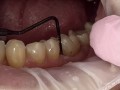

Jednostronne podniesienie zgryzu z zastosowaniem mostu…

Florian Zwiener